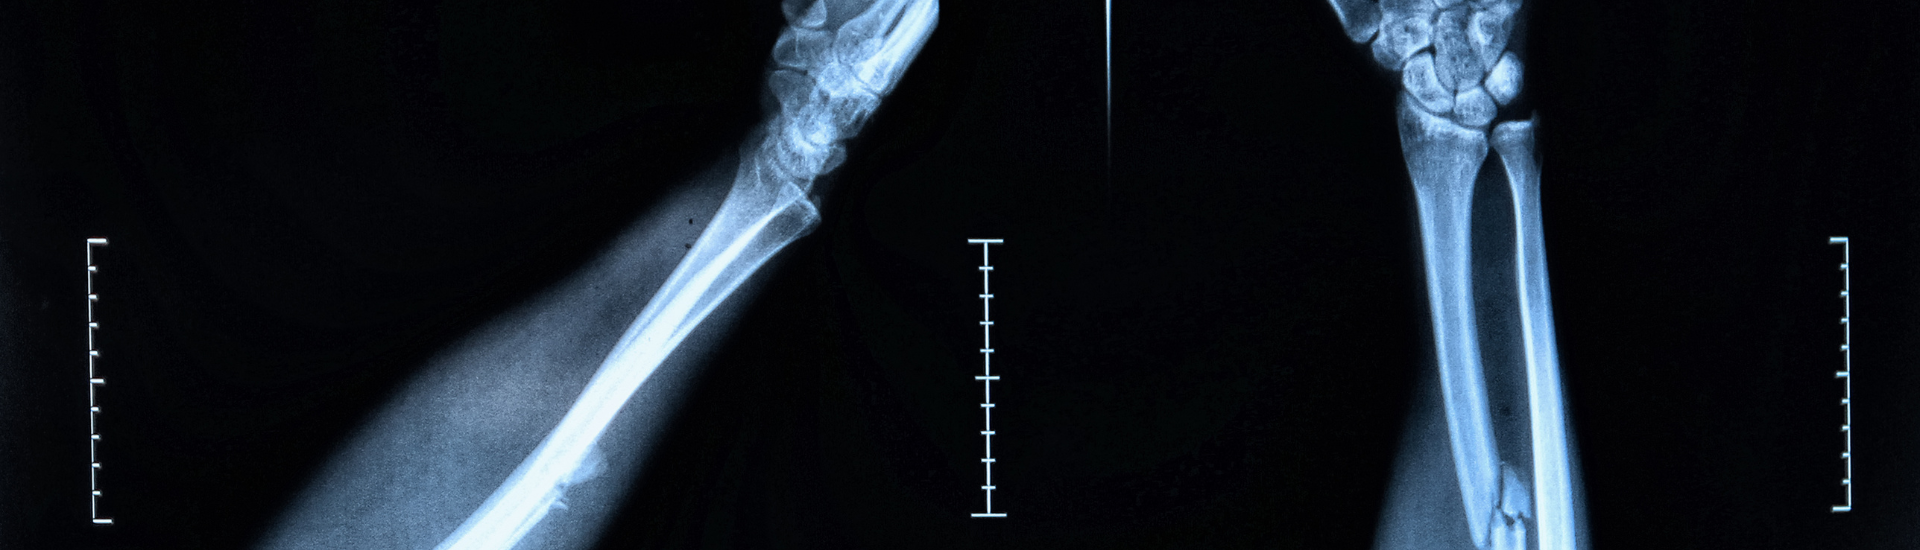

L’Esame RX Braccio, comunemente conosciuto come radiografia del braccio, è un esame diagnostico che utilizza un basso dosaggio di radiazioni ionizzanti per ottenere immagini nitide delle ossa e delle articolazioni del braccio. Si tratta di una procedura non invasiva e indolore, indicata per valutare diverse condizioni patologiche e traumi che possono interessare questa zona del corpo. Le immagini ottenute forniscono informazioni cruciali sulla struttura ossea e permettono di identificare tempestivamente la presenza di lesioni o anomalie.

Come Si Svolge l’Esame RX Braccio?

L’Esame RX Braccio viene eseguito all’interno di una sala radiologica, dove il paziente viene posizionato in modo da permettere al tecnico radiologo di acquisire immagini chiare e complete dell’area da esaminare. Il braccio può essere posizionato in diverse angolazioni, a seconda della zona che deve essere indagata. Durante l’esame, il paziente deve rimanere immobile per evitare che le immagini risultino sfocate. Il tecnico radiologo guiderà il paziente attraverso tutte le fasi dell’esame, assicurandosi che la procedura si svolga nel massimo comfort e sicurezza.

Modalità e Tecnica dell’Esame RX Braccio

Presso il Poliambulatorio S-Medical Group di Sora, l’Esame RX Braccio viene eseguito con apparecchiature moderne che garantiscono una ridotta esposizione alle radiazioni e la massima qualità delle immagini. Il paziente viene preparato dal personale medico, che fornirà indicazioni su eventuali oggetti da rimuovere (come gioielli o indumenti metallici) prima di eseguire l’esame. La procedura dura pochi minuti e non richiede un periodo di riposo successivo, consentendo al paziente di tornare immediatamente alle proprie attività quotidiane.